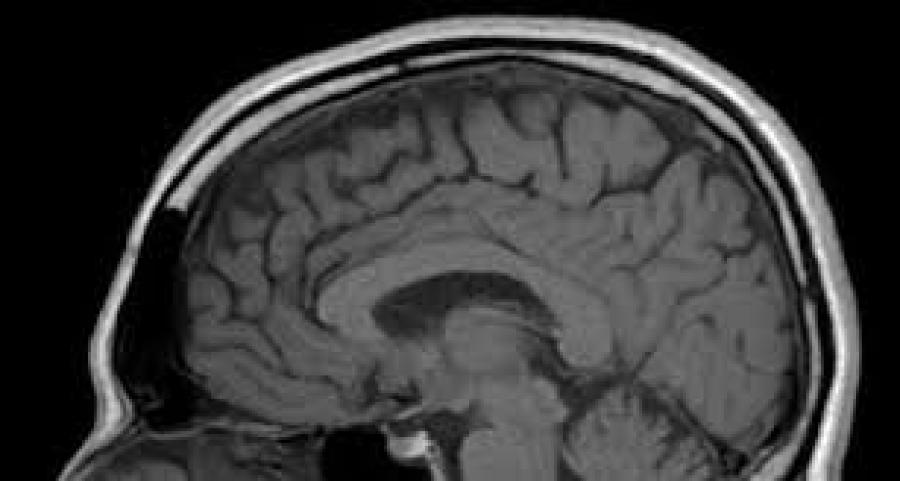

Clinicians tend to avoid the word concussion, preferring to describe it in terms of brain injury, trauma, and perhaps because of this the word concussion does not generate the sense of alarm it once did.

Only in quite recent times has concussion as a trauma re-entered the public medical consciousness and it has done so in concert with the wider perception of dementia and its early onset.